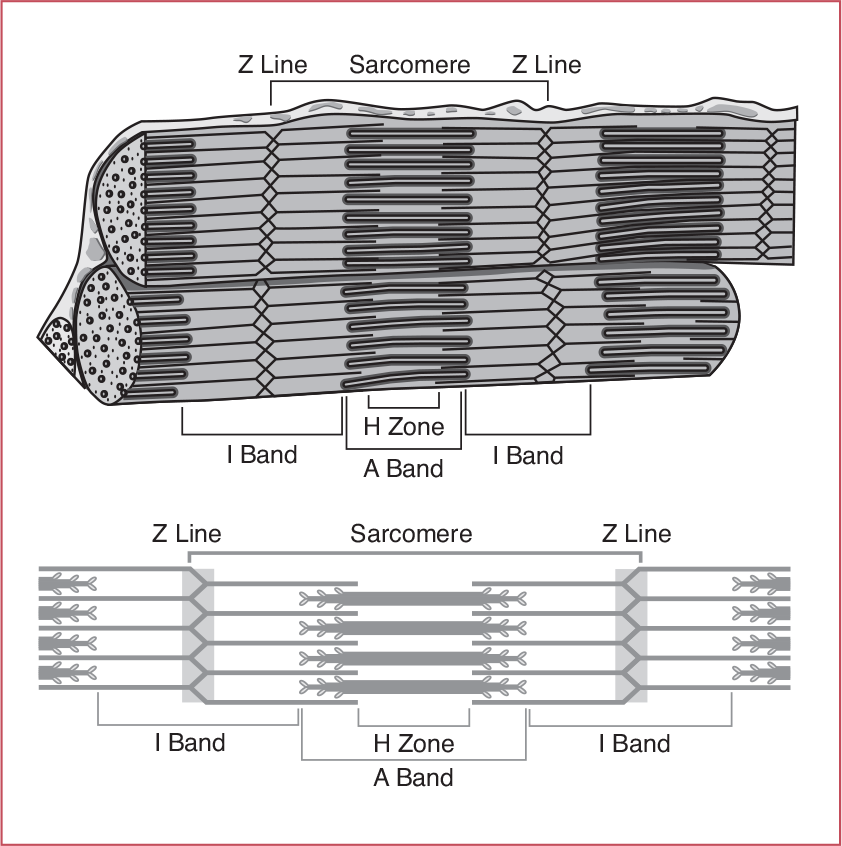

Please describe the A band, H Zone, and I band

- A band: Myosin

- H zone: Myosin not overlapped with Actin

- I band: Actin not overlapped with Myosin

What allows for muscle fiber relaxation?

ATP powering Ca++ being pumped back into the sarcoplasmic reticulum allowing tropomyosin to block actin’s active sites